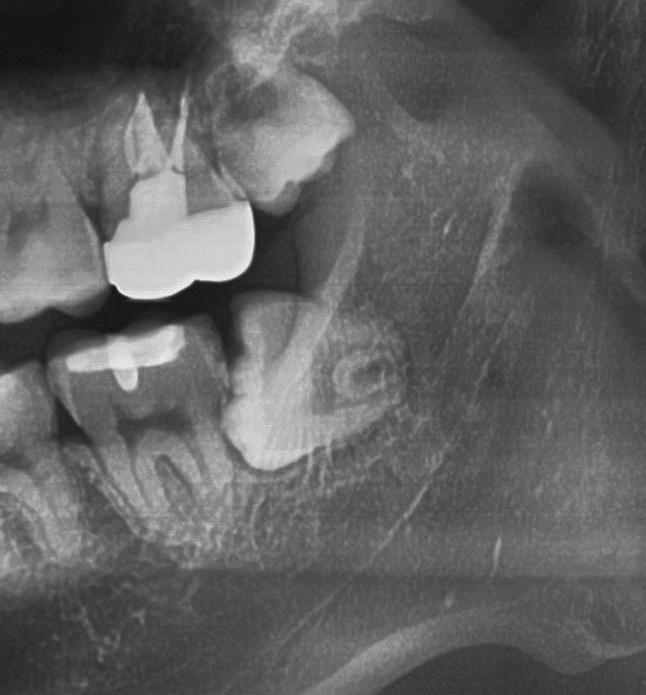

5.2.5 Un caso di un’estrazione di un dente del giudizio, utilizzando il manipolo dritto, da parte di un altro dentista

L’estrazione di un dente del giudizio incluso orizzontalmente, sfruttando questa tecnica con il manipolo dritto, richiede un’ulteriore rimozione di struttura dentale e di osso. Figg. 180-183

Per questo motivo, il lembo deve essere esteso fino al primo molare e bisogna avere una visione del sito chirurgico adeguata. Più il dente è inclinato orizzontalmente più la rimozione di osso vestibolare è necessaria.

Solitamente viene utilizzata una fresa a fessura dritta da manipolo per sezionare le radici, ma è preferibile usare una fresa rotonda laddove c’è la necessità di rimuovere l’osso alveolare attorno alla corona, come mostrato in fotografia. Figg. 184-187

In questo caso la separazione del periostio e la rimozione di osso vestibolare è quasi inevitabile per estrarre il #38.